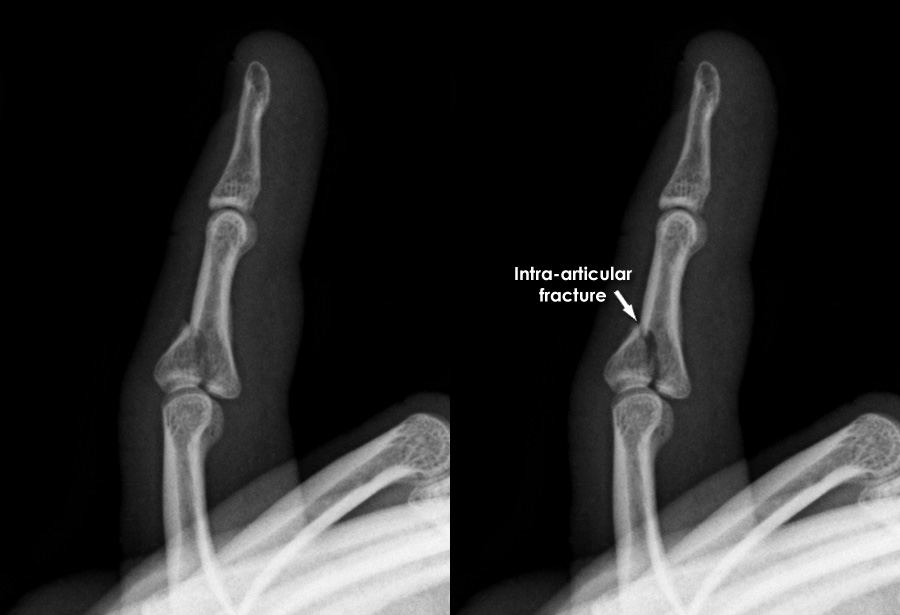

Finger Jam Vs Fracture some common symptoms of a jammed finger include pain in the injured area, redness and swelling, weak feeling in the finger, and inability to extend the finger fully. Rarely requires surgery or splinting. that said, sometimes, an injury results in a jammed finger, which may have a quick fix, while other injuries may result in a fracture. You put out your hand to break a fall. Your finger jams while trying to catch a ball. depending on how badly you injured yourself, it may be hard to tell the difference between a jammed and broken. While they may share similar symptoms, understanding the differences between them is crucial for proper diagnosis and appropriate treatment. It’s what usually happens when you shut a door or a drawer on your hand. On the other hand, a broken or fractured finger occurs when the finger bone actually cracks. you can fracture a finger when: two common finger injuries often misjudged are a jammed finger and a broken finger. You have an accident while. Redness and swelling that starts to recede after a little while. Jamming a finger is a prevalent sports injury often due to having your hand absorb the impact of catching a ball. a few key differences between a jammed or broken finger: a jammed finger occurs when a person injures one of the finger joints.